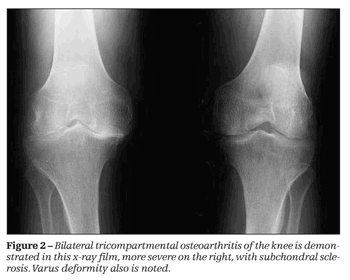

Synovitis predates and is associated with the development of radiographic osteoarthritis, new findings suggest. Treating synovitis in knee OA may help reduce disease progression and relieve symptoms. Details here.